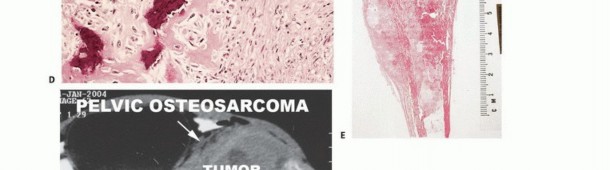

Chondrosarcoma

Chondrosarcoma is the most common primary malignant bone tumor of the hand. It often arises in the proximal phalanges or metacarpals, sometimes secondary to a pre-existing enchondroma. Patients typically present with a painful, enlarging mass. Radiographs show aggressive bone destruction, cortical breakthrough, and soft tissue extension.

Surgical Management:

* Ray Amputation: For lesions confined to a single digit or metacarpal, a radical ray amputation provides definitive wide margins.

* Limb Salvage: In select cases involving the carpus or distal radius, wide en bloc resection followed by complex reconstruction (e.g., wrist arthrodesis with vascularized fibular graft) may be attempted, provided negative margins can be achieved.

Management:

Surgical intervention for Paget's disease in the hand is rarely indicated unless there is a pathologic fracture or severe deformity causing functional impairment. Medical management with bisphosphonates is the primary treatment modality to decrease bone turnover and alleviate pain. If surgery is required (e.g., corrective osteotomy or fracture fixation), the surgeon must be prepared for highly vascular bone and the potential for delayed union. Furthermore, any sudden increase in pain or rapid swelling in a Pagetic bone must raise the clinical suspicion for malignant transformation to secondary osteosarcoma, which carries a grave prognosis.